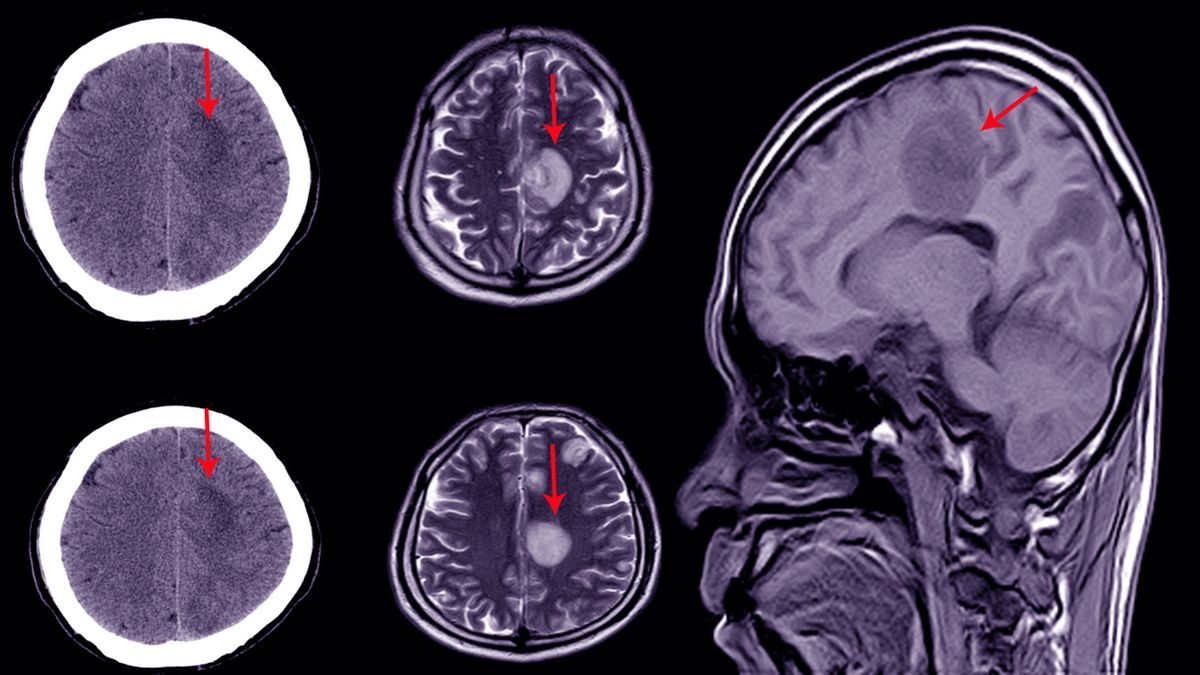

• Tomografia komputerowa głowy. Typowe jest poszerzenie światła komór bez oznak zaników splotu naczyniówkowego.

• Rezonans magnetyczny głowy. Charakterystyczne jest nasiąkanie wysiółki komór przez płyn oraz poszerzenie układu komorowego oraz wodociągu mózgu.